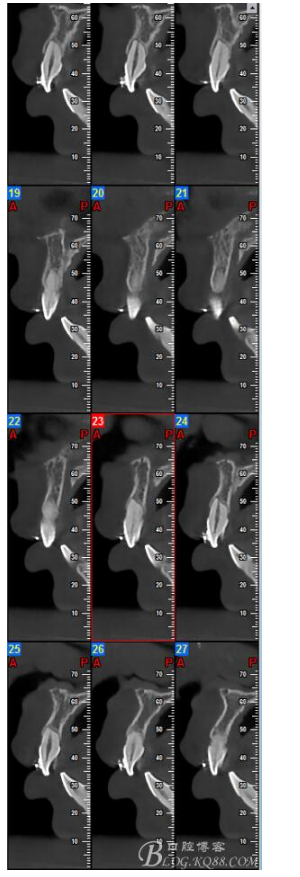

鐘佳溪:正畸治療不可忽視的副作用——牙根再吸收

大多數(shù)研究認同牙根再吸收的嚴重性與正畸治療的持續(xù)時間、力量大小相關。臨床醫(yī)師應該采用輕力、高效的矯治手段進行正畸治療,并在正畸治療前、中、后進行X線檢查對比,觀察牙根再吸收的發(fā)生情況。研究發(fā)現(xiàn):間斷治療的患者其牙根再吸收量明顯少于那些持續(xù)治療的患者。應用力的中斷有助于已破壞的牙周組織重建并減少牙根的進一步縮短。